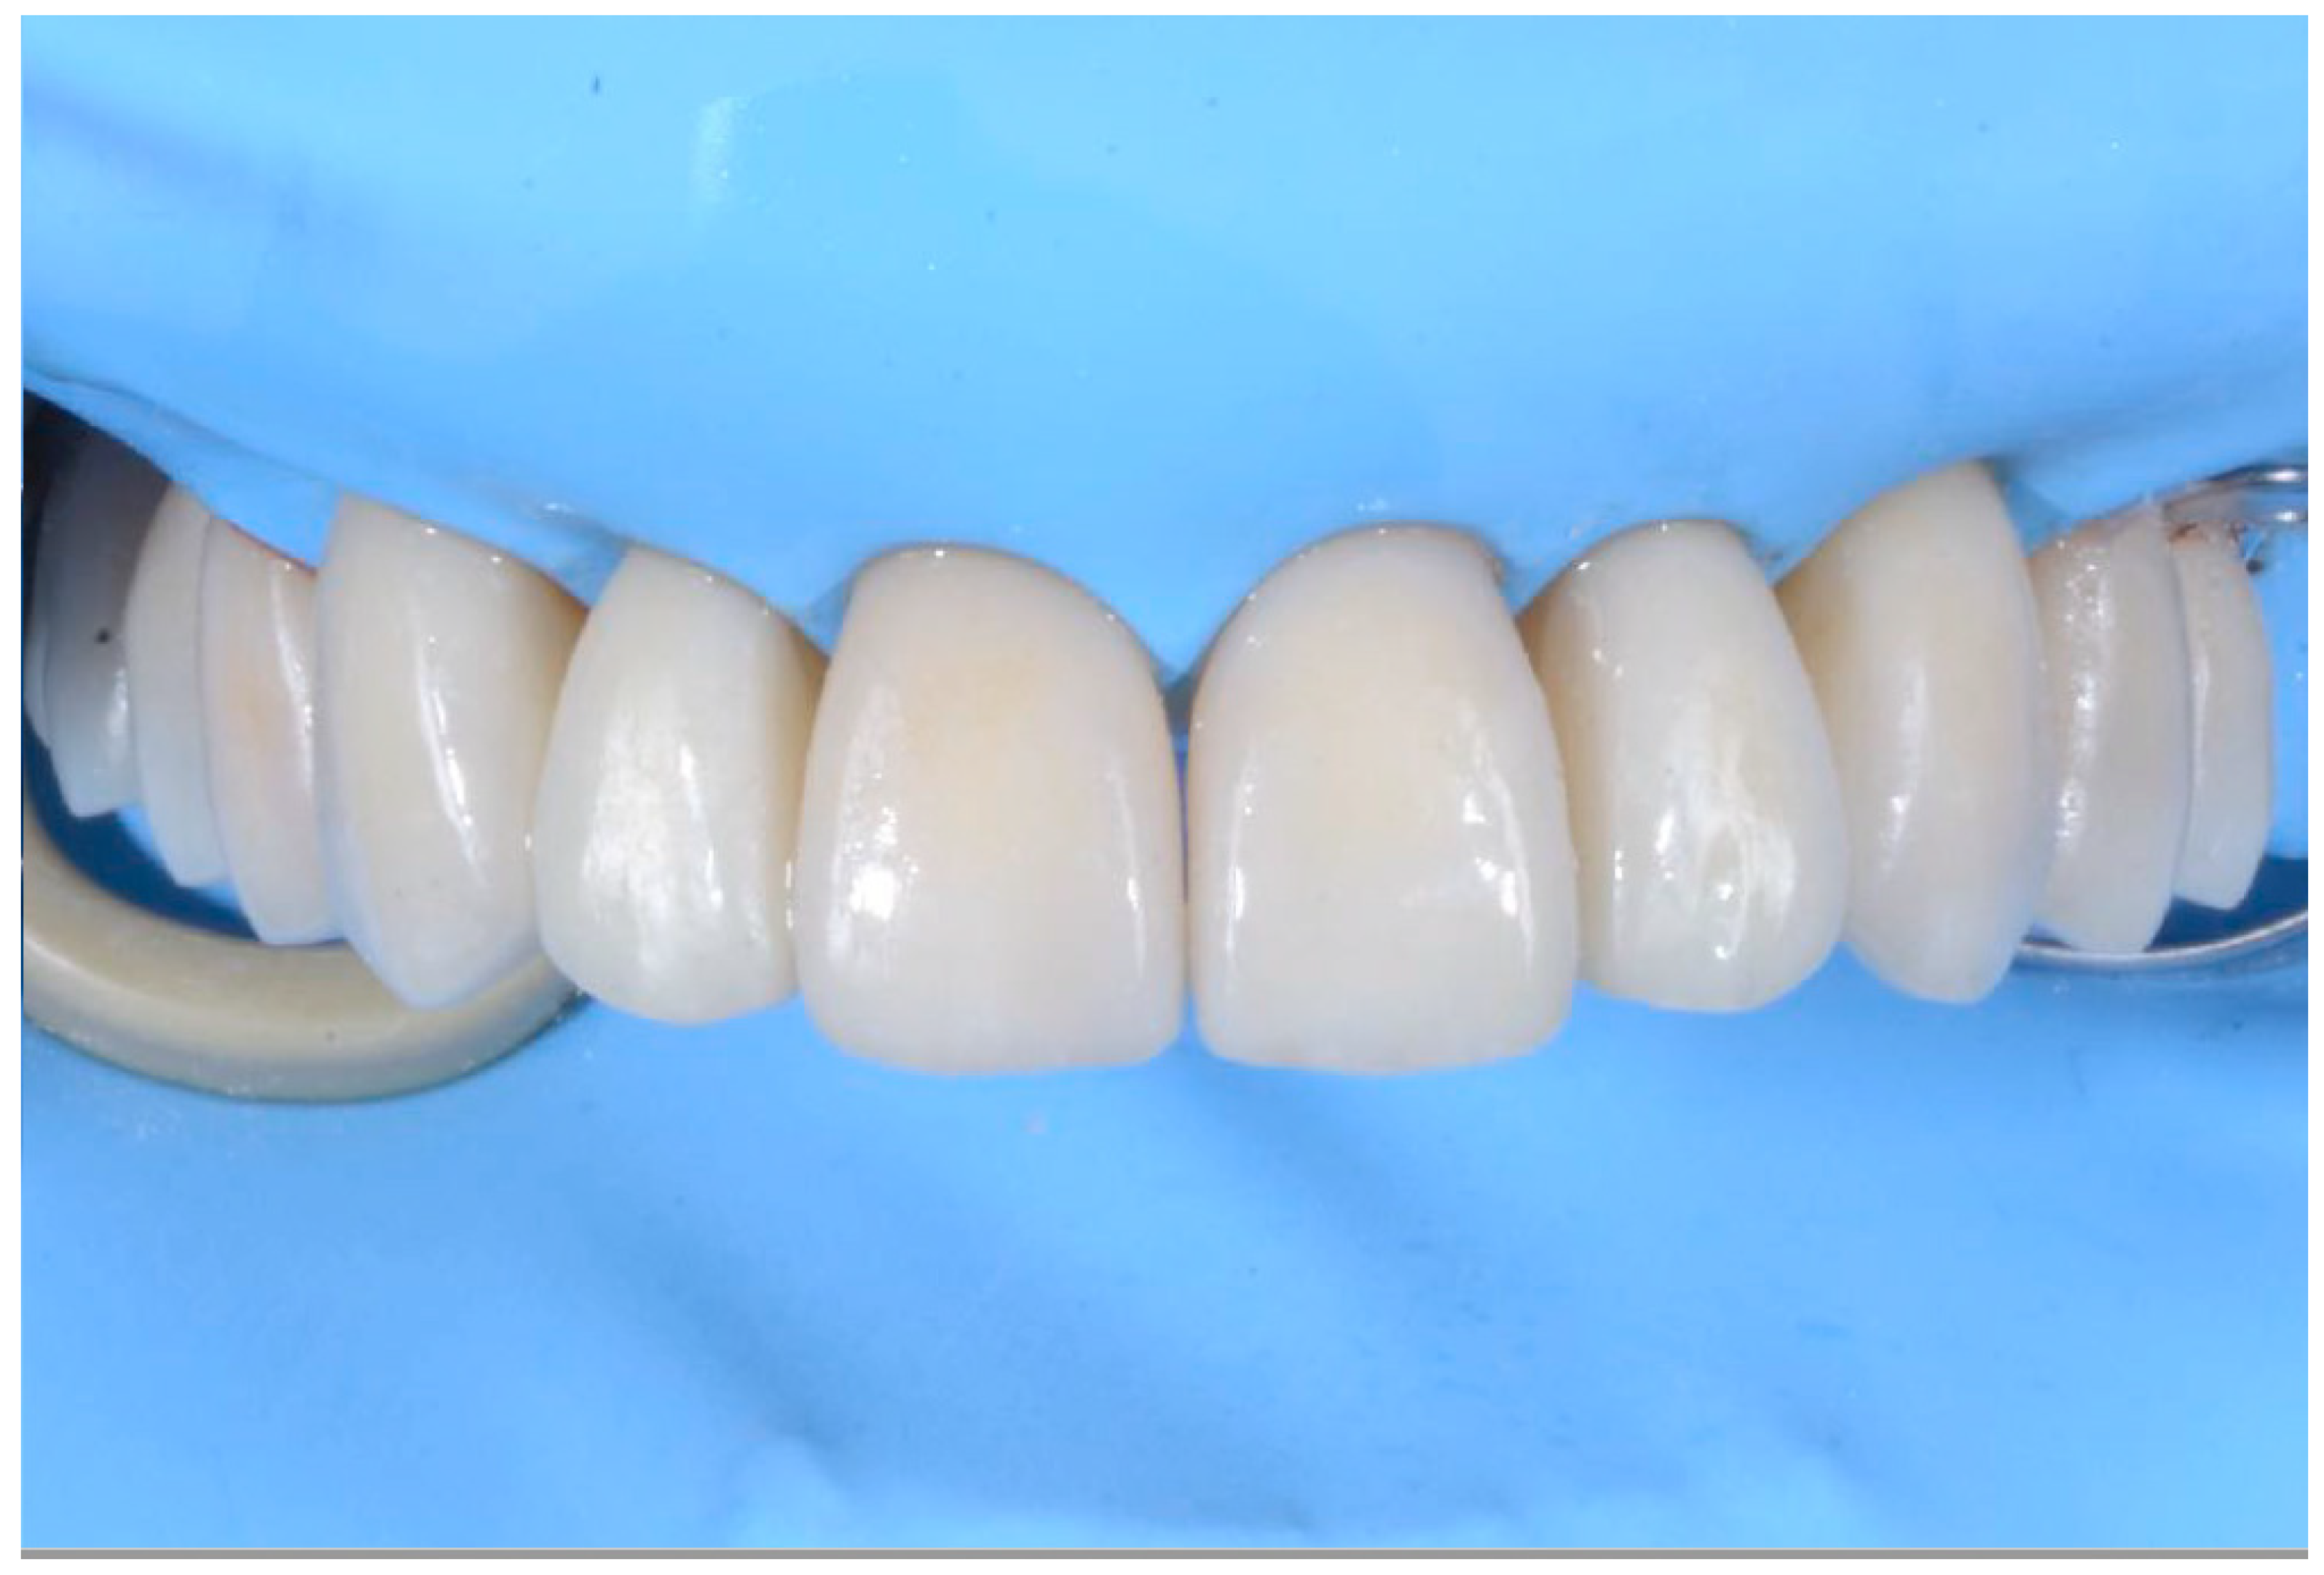

2.3. Outcome Achieved